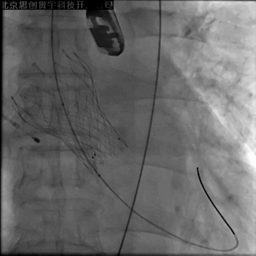

22mm球囊后扩

复查彩超,瓣膜贴壁良好,无瓣周漏,残余压差<10mmHg

术后即刻LVEF 35.4%,较术前显著改善